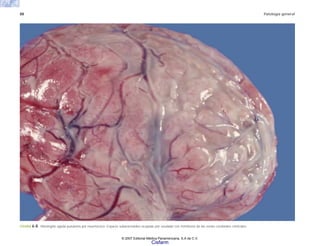

FIGURA 6-31. a) Vasculitis coronaria en un caso de SIDA que muestra necrosis